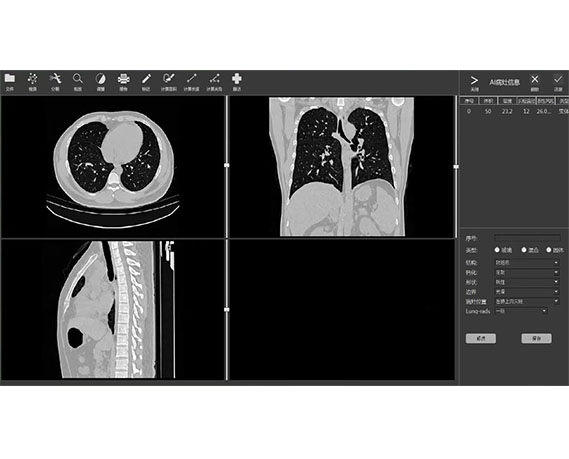

ANYTHINK 经导管主动脉瓣膜置换术分析系统